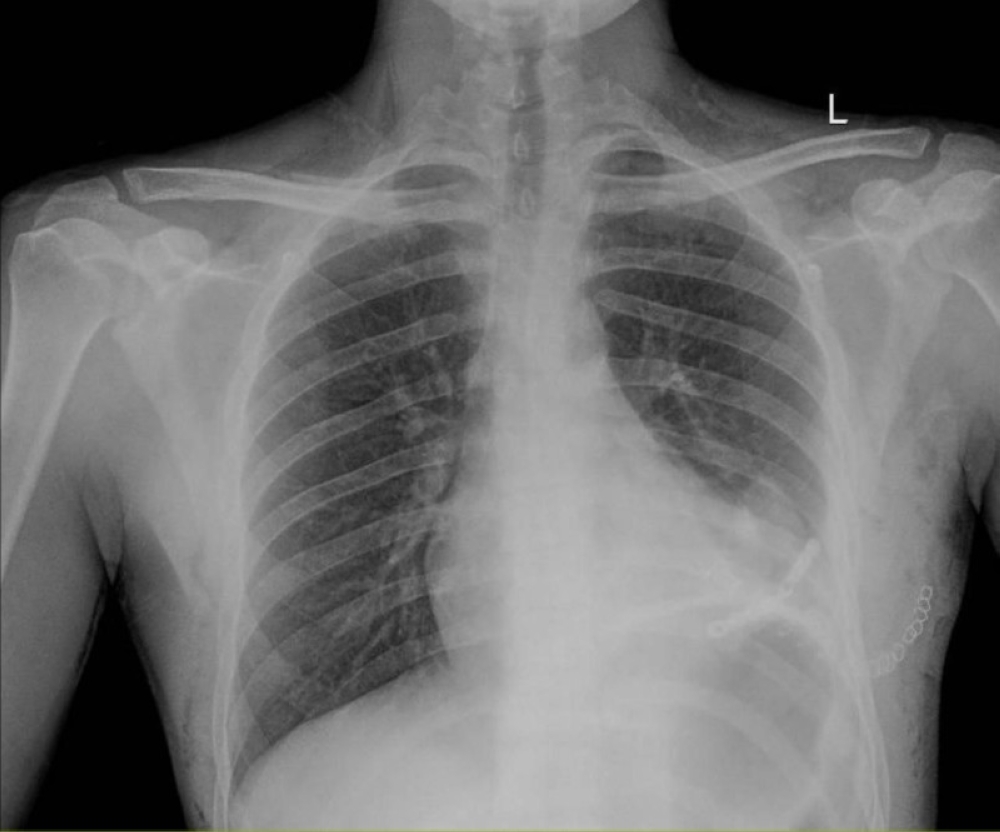

وقد استقبلت طوارئ المدينة الحالة بشكل عاجل عن طريق برنامج «إنقاذ الحياة»، بعد تحويله من أحد المستشفيات الخاصة بالرياض، وكان المريض في حالة غير مستقرة، على جهاز التنفس الصناعي، ويعاني من نزيف نشط عبر الأنبوب الصدري نتيجة استرواح دموي شديد.

وبشكل عاجل، أُجري تدخل جراحي طارئ لاستكشاف الصدر والقلب، حيث تبين وجود إصابة نافذة في عضلة البطين الأيسر بطول 5 سم، إلى جانب تهتك في الرئة اليسرى وكسر في أحد الأضلاع. وتمكن الفريق من السيطرة على النزيف، وإصلاح القلب والرئة، وتثبيت الكسر باستخدام شريحة من التيتانيوم.

The emergency department received the case urgently through the "Life Saving" program after he was transferred from a private hospital in Riyadh. The patient was in an unstable condition, on a ventilator, and suffering from active bleeding through the chest tube due to severe hemothorax.

An emergency surgical intervention was urgently performed to explore the chest and heart, where a 5 cm penetrating injury was found in the left ventricular muscle, along with laceration in the left lung and a broken rib. The team was able to control the bleeding, repair the heart and lung, and stabilize the fracture using a titanium plate.